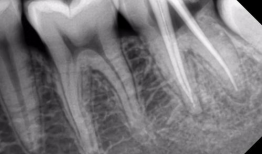

根管治疗视频,从视频学习根管治疗技巧与流程

最近是不是牙齿疼得你坐立不安,连笑容都变得苦涩了呢?别担心,今天就来给你揭秘一下那个听起来有点吓人的根管治疗,让你对这个过程有个...

2025-09-01 273 -